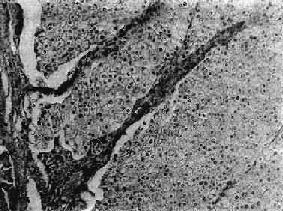

图12-27 肾透明细胞癌 癌细胞呈多角形或立方形,轮廓清楚,胞浆透明,核居中,深染。癌细胞排列成片状,间质很少